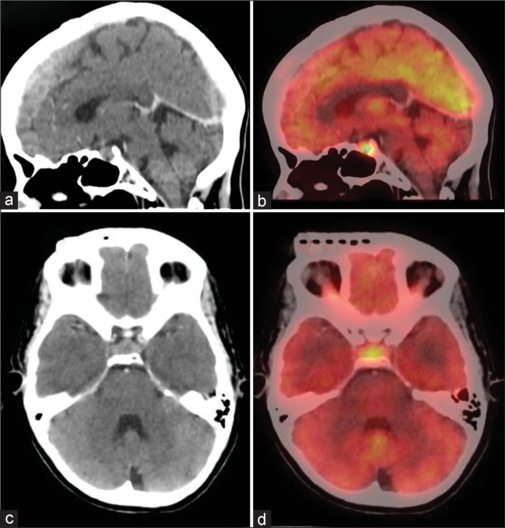

Lung cancer is the leading cause of cancer and cancer-related deaths, and India ranks the fourth highest country. Lung cancer is a highly aggressive malignancy with a tendency for rapid progression, making early detection and prompt treatment essential for improving patient outcomes. Lung cancer can spread locally into surrounding tissue as well as travel through lymphatics to other parts of the body, most often to bone, brain, liver, and adrenal glands. Metastasis to pituitary and pineal glands is extremely rare. The differential diagnosis for pituitary metastasis could be pituitary adenoma where lesion usually lies at the anterior aspect of pituitary fossa, whereas metastasis is seen at the posterior aspect. There is a paucity of published literature, with only a few cases reported of pituitary and pineal gland metastasis. Hence, to add to the literature, we present a case of pituitary metastasis in an older woman with lung cancer.